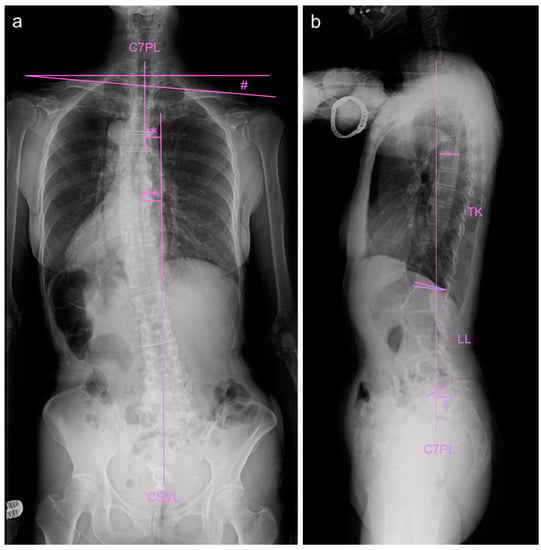

2.2. Image Examinations at First Visit